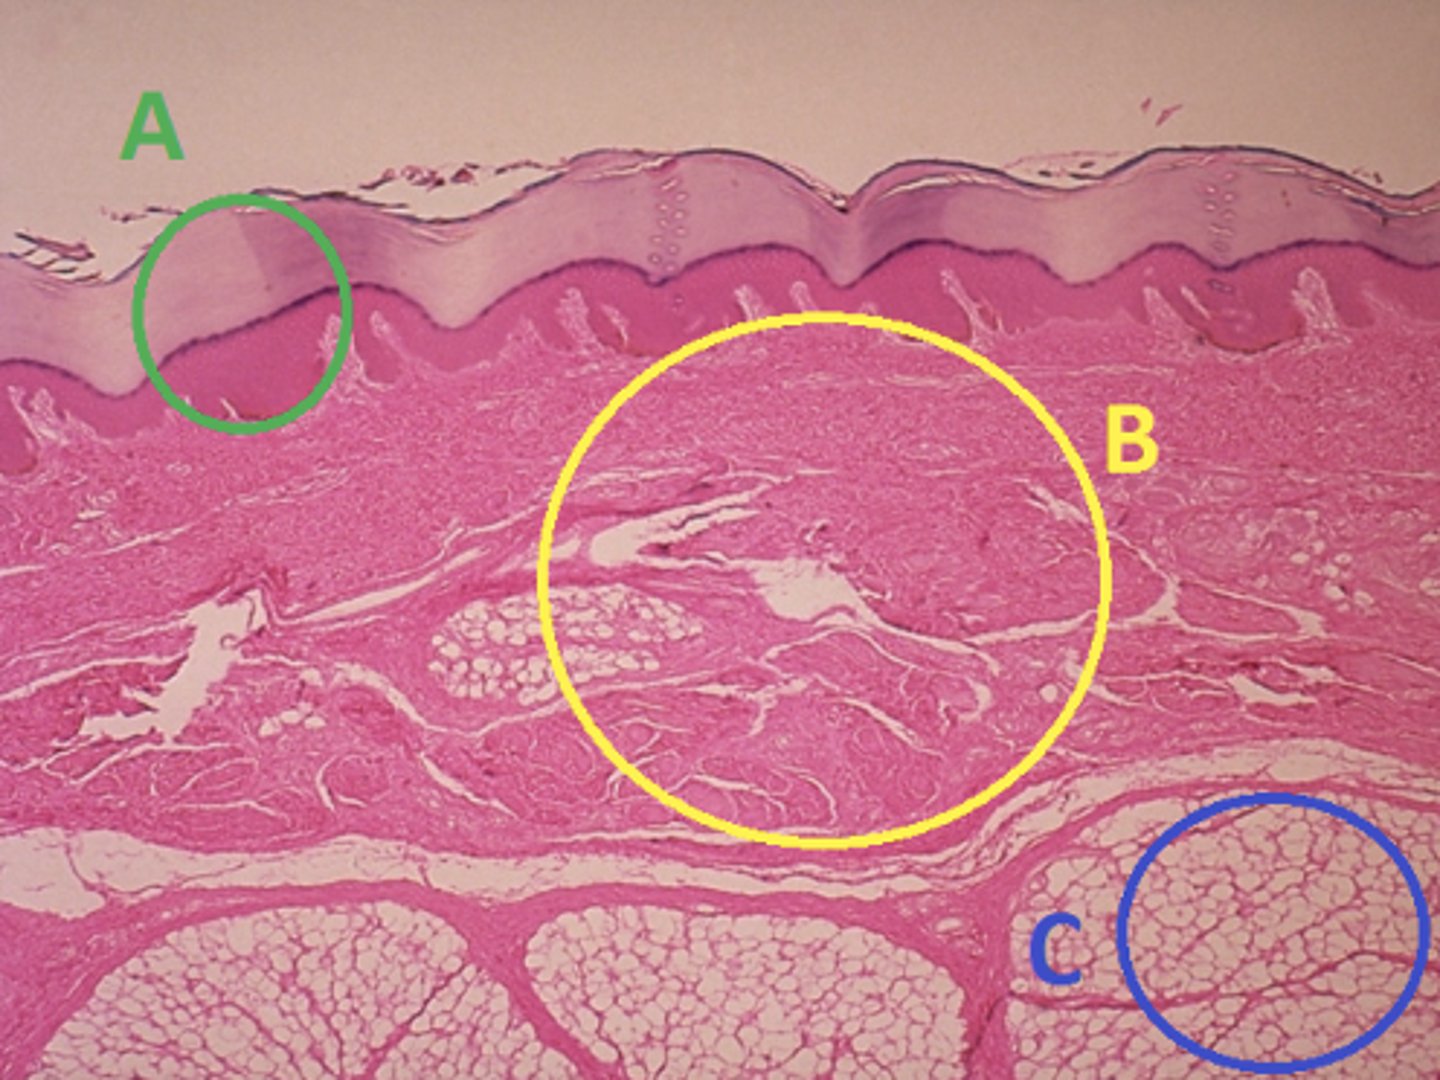

C - hypodermis

Answer the following questions based on the features indicated in the following image. Which letter indicates the administration site for subcutaneous injections?

A - epidermis

Answer the following questions based on the features indicated in the following image. Which letter indicates the administration site for topical creams and ointments?

B - Dermis

Answer the following questions based on the features indicated in the following image. Which letter indicates the administration site for the tuberculin skin test?

A - epidermis

Answer the following questions based on the features indicated in the following image. Which letter indicates a region of the skin with no nerves or blood vessels?

B - Dermis

Answer the following questions based on the features indicated in the following image. Which letter indicates the region where skin appendages (sweat glands, sebaceous glands, and hair follicles) have their roots?

Epithelial tissue

Answer the following questions based on the features indicated in the following image. Which of the four major tissue types is indicated by letter A?

Skin of the soles of the feet

Where would hair follicles be absent?

Skin in the axilla (armpit)

Skin on the back of the hand

Skin of the dorsal surface of the feet

Skin of the soles of the feet

C

Which letter indicates the administration site for insulin injections?

A

Which letter indicates the administration site for a lidocaine patch?

B

Which letter indicates the administration site for an allergy test?

B

Which letter indicates a region of the skin rich in dense, irregular connective tissue?

C

Which letter indicates the region most important for energy storage and thermal insulation?

Connective

Which of the four major tissue types is indicated by letter C?

Skin of the dorsal surface (back) of the hand

Which part of the body could the previous image represent?

Skin of the ventral surface (palm) of the hand

Skin of the dorsal surface (back) of the hand